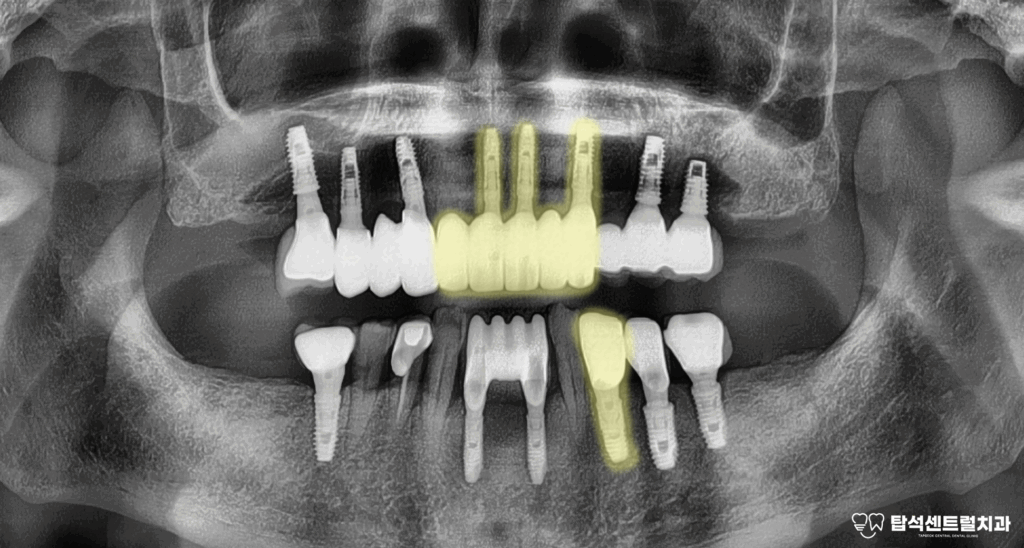

골소실과 동요도가

나타났다면

치아 주변으로 골소실이 진행되면

방사선 사진에서 뼈가 빠져나간 부분이

검게 보이게 됩니다.

예를 들어 위턱 앞니 부위에 심은

브릿지 형태의 보철을 살펴보면

여러 개의 고정체가 연결되어 있어도

특정 부위에만 골소실이 집중될 수 있습니다.

한쪽은 상태가 양호하더라도 다른 쪽에

임플란트 주위염이 발생하면

해당 부위만 선택적으로 제거하고

새로운 치료 계획을 수립하게 됩니다.

제거한 픽스처의 모습입니다.

다행히, 왼쪽 위턱의 송곳니는 상태가 양호하여

임플란트 한개 제거 후 장기적인 안정성을

위해 앞니에 2개의 임플란트 를

추가 식립한 모습입니다.

이때, 결손되어 비어 있었던

아래 작은 어금니쪽에도

임플란트 하나를 같이 심어주었습니다.